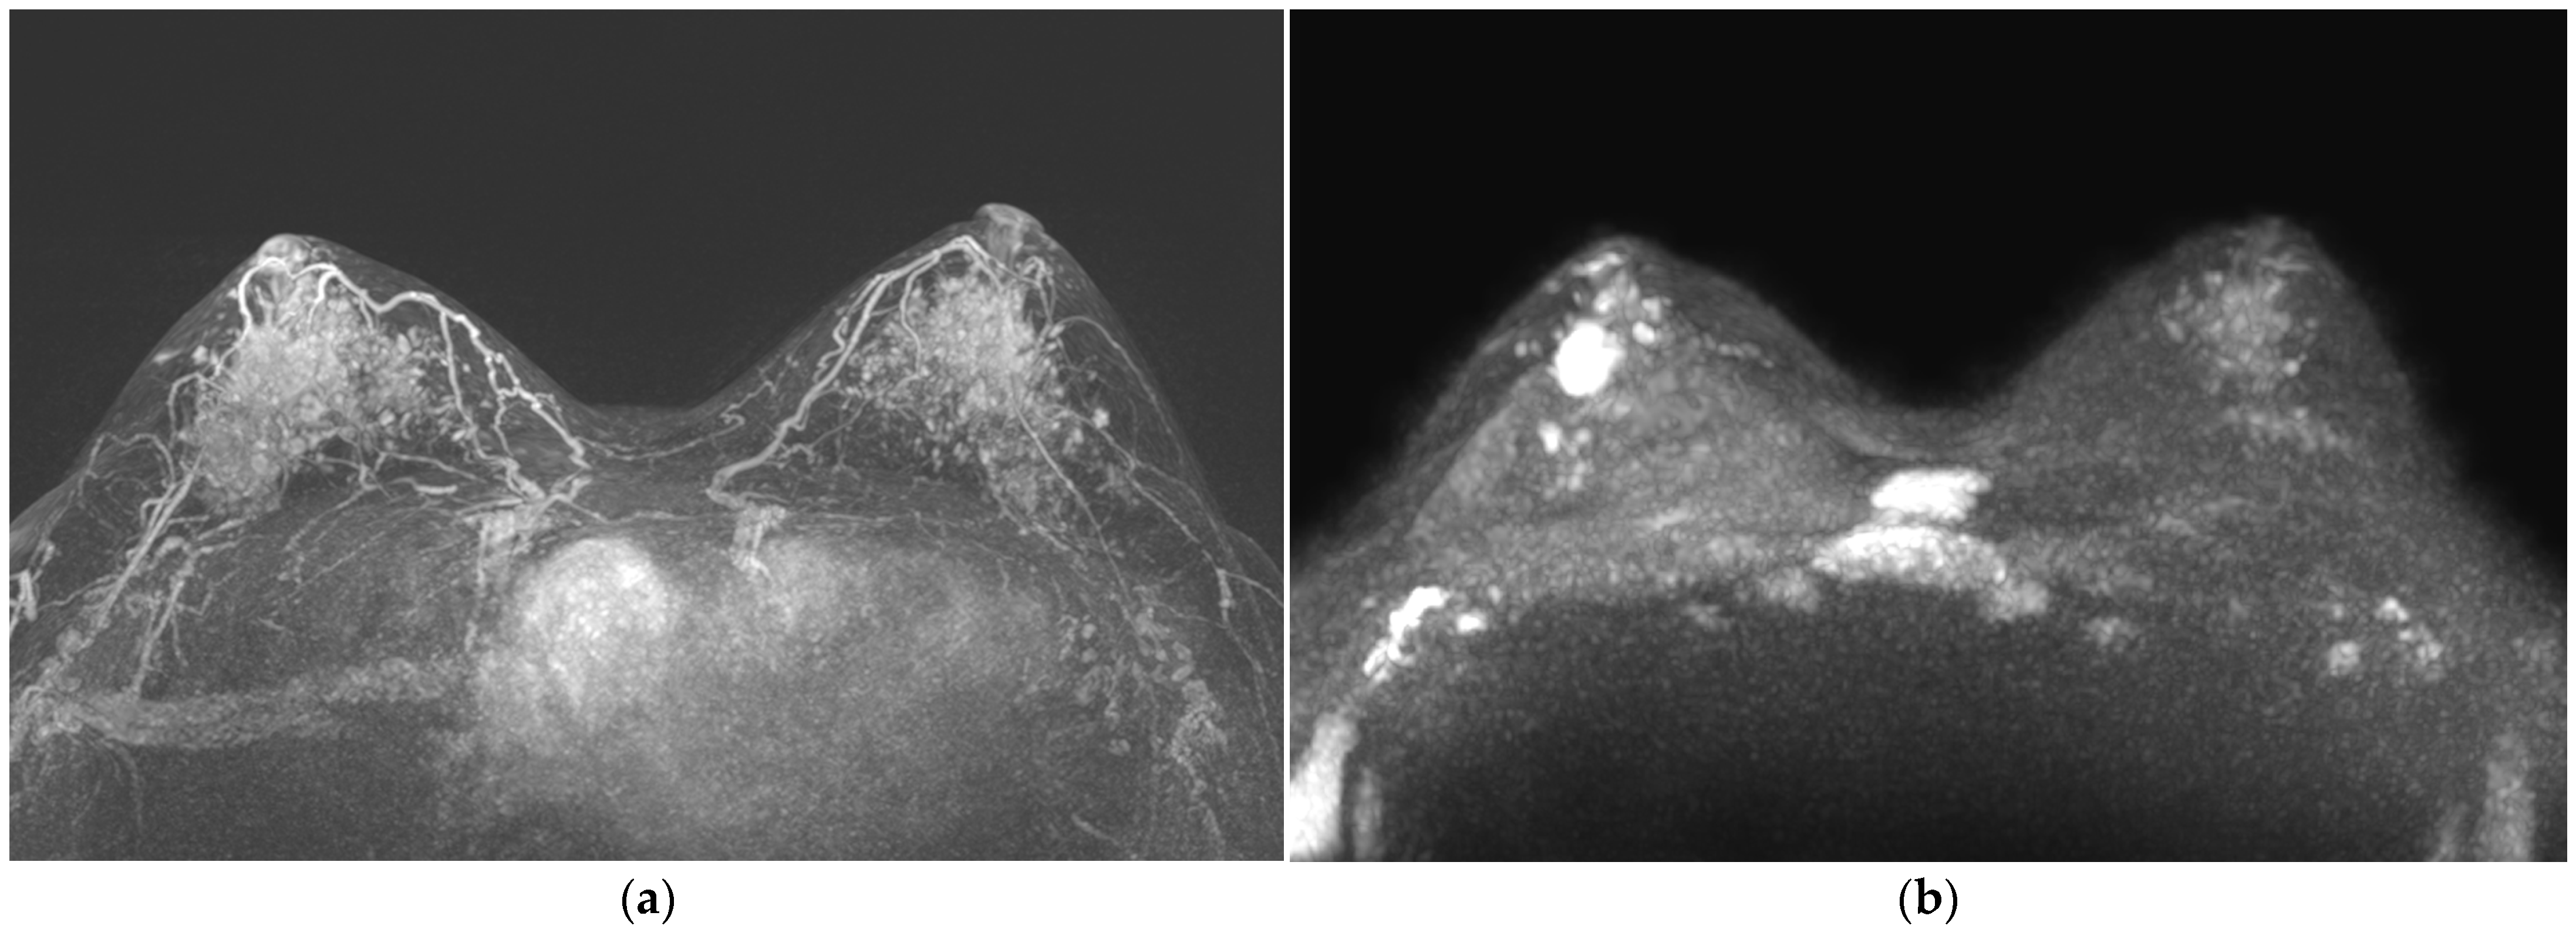

3. Results